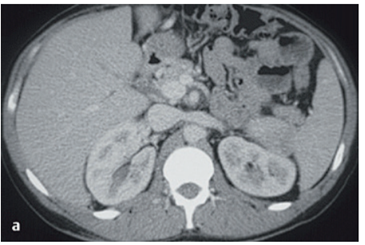

Analise a imagem abaixo. Em seguida, marque o item correspondente ao exame de imagem e ao/a corte/incidência em questão.

Fonte:JUNIOR, Carlos Fernando de M. Radiologia Básica. 3. ed. Rio de Janeiro: Thieme Revinter, 2021. E-book. p.2